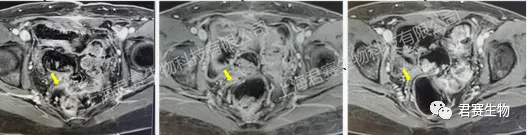

受试者接受TIL回输前、回输后6周及回输后12周影像资料